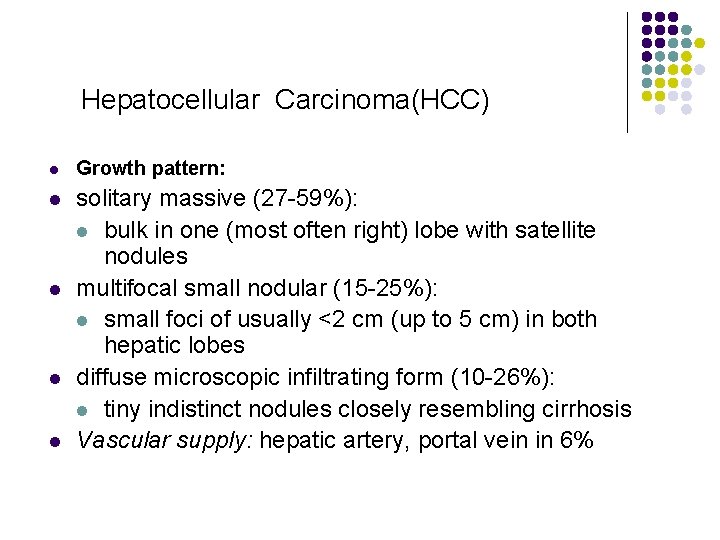

Hepatocellular Carcinoma(HCC) l Growth pattern: l solitary massive (27 -59%): l bulk in one (most often right) lobe with satellite nodules multifocal small nodular (15 -25%): l small foci of usually <2 cm (up to 5 cm) in both hepatic lobes diffuse microscopic infiltrating form (10 -26%): l tiny indistinct nodules closely resembling cirrhosis Vascular supply: hepatic artery, portal vein in 6% l l l